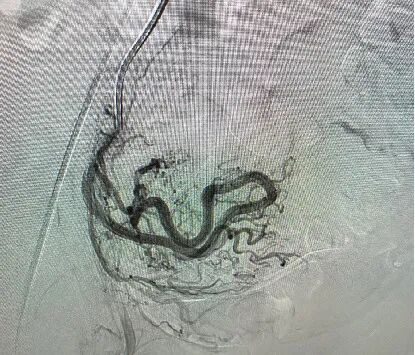

他们决定为她行动脉栓塞术,这是一种微创介入治疗。医生从患者大腿根部的血管插入一根细导管,在X光引导下,将导管精确送到给这个血管团供血的子宫动脉分支。

然后注入一种叫明胶海绵颗粒的栓塞剂,这些颗粒就像无数小沙子,随着血流堵住畸形血管团的供血血管,使其内部形成血栓,最终让这个血管团萎缩消失。

手术非常成功,几个月后复查血管核磁共振,显示那个血管团已经显著缩小,血流信号几乎消失。